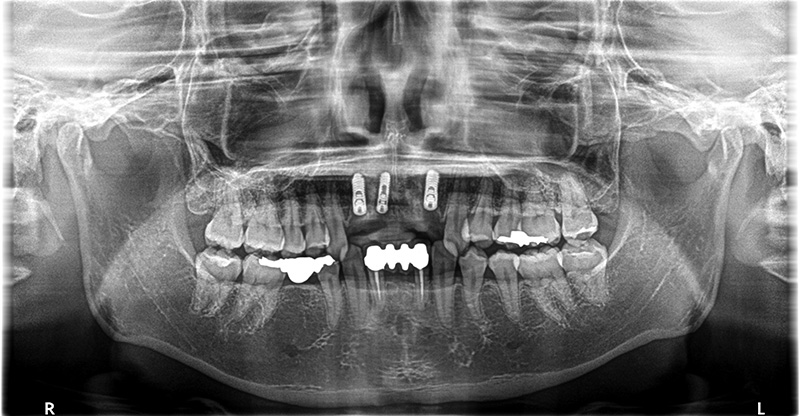

歯根に膿が溜まっているため抜歯しインプラントで修復した症例

こちらの患者さまは、前歯がぐらついていて噛むと痛いとの主訴で来院されました。

レントゲンでの検査の結果、過去に他院で治療した歯の根が感染を起こし、歯根に膿が溜まっていることが確認できました。

膿の袋がかなり大きく、骨欠損の範囲が大きかったため、再根管治療での回復が見込めず、完治の可能性が低いが再度、再根管治療を行うか、成功率の高いインプラントでの治療を行うかと相談したところ、抜歯、インプラントでの治療を希望され、行うことになりました。